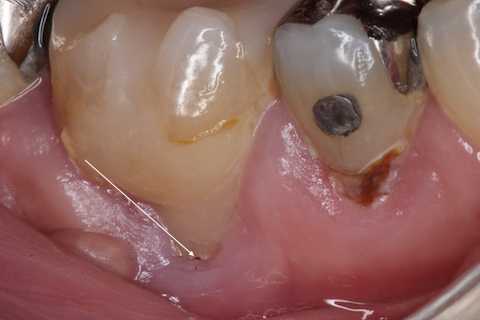

残根上のCR8 2025.10.28